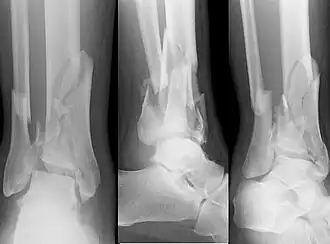

![]() Fractura de pilón tibial asociada a fractura de peroné | ||

En medicina, se denomina fractura de pilón tibial a un tipo de fractura de tibia que se caracteriza por afectar tanto a la epifisis distal como a la metáfisis del hueso, comprometiendo la articulación del tobillo. Es un tipo de fractura de gran complejidad y de pronóstico grave, existiendo dificultades para alcanzar la curación completa, pudiendo quedar secuelas permanentes.[1][2]